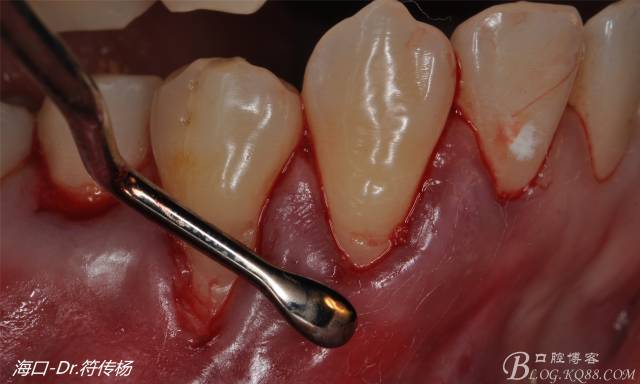

首先用顯微手術(shù)刀切斷手術(shù)范圍內(nèi)的牙周韌帶

然后使用下頜開隧刀剝離牙齦